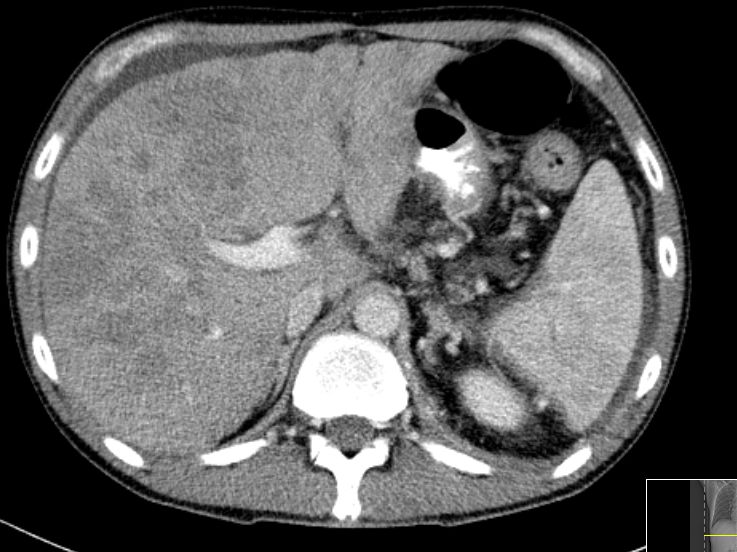

| Lokalrezidiv | 77-jährige Frau 9 Monate nach pyloruserhaltender Pankreaskopfresektion. Das Rezidiv hat die Vena portae eingegengt.![]() |